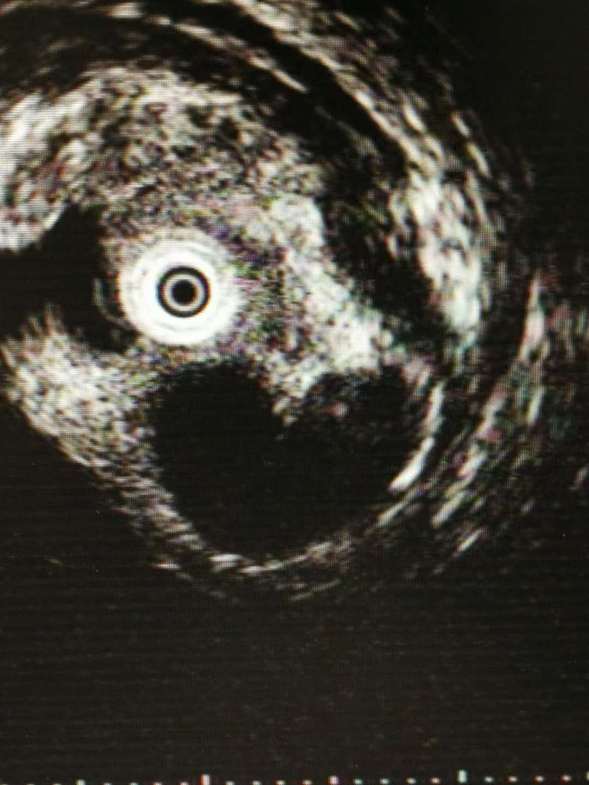

超声内镜下显示爱心形瘤体